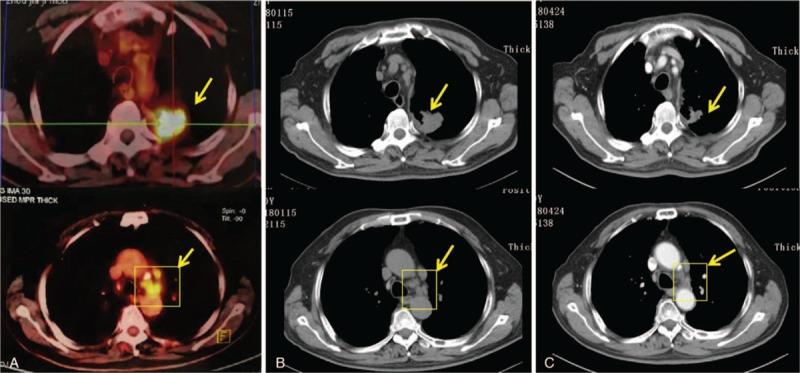

Needle biopsy and positron emitted tomography/computed tomography were performed. The patient was diagnosed with advanced NSCLC adenocarcinoma with bone and lymphatic metastasis. Next-generation sequencing of circulating tumor DNA was performed, which identified a p.A289V mutation in the EGFR gene of the patient.

进行了穿刺活检和正电子发射断层扫描/计算机断层扫描。患者被诊断为晚期NSCLC腺癌伴骨和淋巴结转移。对循环肿瘤DNA进行了二代测序,结果显示患者的EGFR基因存在p.A289V突变。